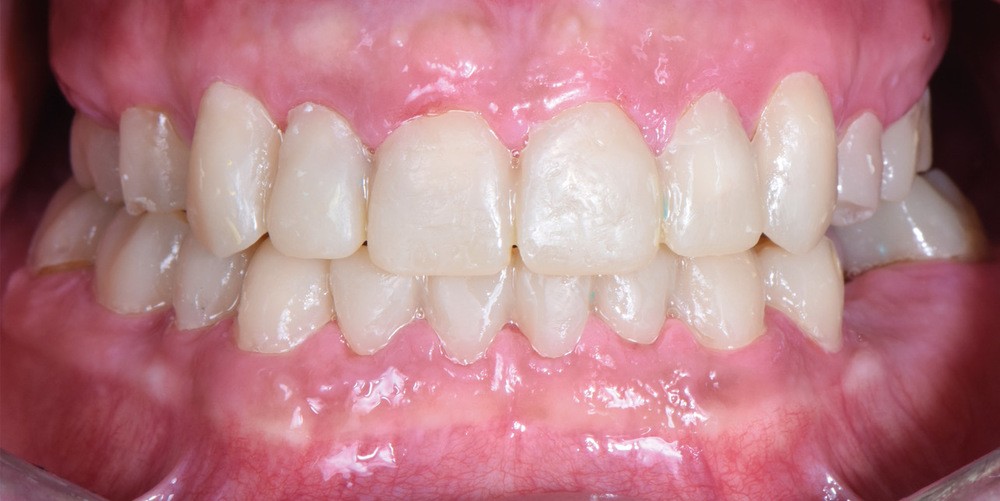

Au vu du contexte para-fonctionnel et de l’étendue de la perte tissulaire, des coiffes périphériques minimalement invasives ont été choisies afin de restaurer l’esthétique et la fonction. Actuellement, aucun consensus n’est fait sur le choix du matériau d’infrastructure à privilégier. Les matériaux hybrides usinables présentent des propriétés mécaniques, physiques et biologiques intéressantes en contexte d’usure sévère (e.g., module d’élasticité, résistance à la propagation de fêlures, facilité de réintervention). Une réhabilitation globale avec remontée de dimension verticale d’occlusion (DVO) par l’intermédiaire de coiffes composites renforcés en nano-céramiques est décrite.